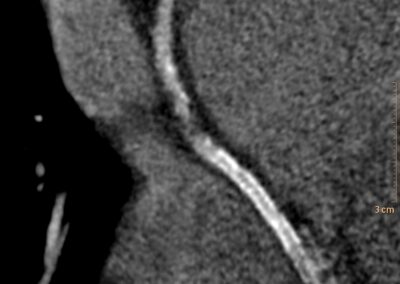

στεφανιογραφία στον αξονικό τομογράφο.

Τρισδιάστατη και δισδιάστατη απεικόνιση των στεφανιαίων αγγείων όπου διακρίνεται σημαντικότατη στένωση της δεξιάς στεφανιαίας αρτηρίας λίγο πριν το προϋπάρχον stent, το οποίο απεικονίζεται φυσιολογικά βατό